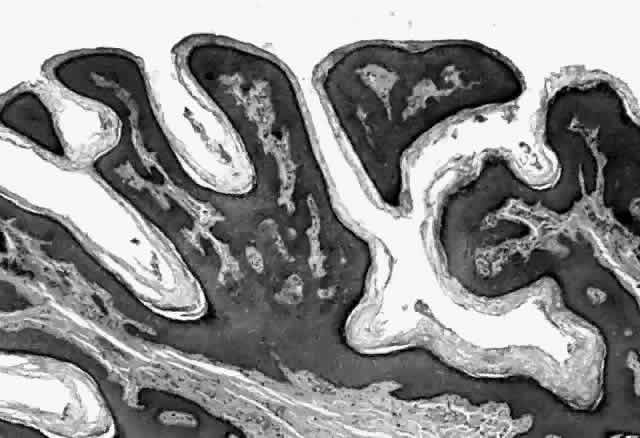

HPV-induced conjunctival squamous papillomas demonstrate papillomatosis, acanthosis, and koilocytosis (Fig. 6). Because they are mucous membrane lesions, those of the conjunctiva and lacrimal sac show no granular cell layer but will show keratinization if they are large or exposed (Fig. 7). In our experience the frequency of koilocytes is variable, even in lesions almost certain to be viral (Fig. 8). Scattered inflammatory cells may be present in the cores or epithelium. Virus can be detected immunohistochemically in the nuclei of the cells (Fig. 9).

Fig. 6. Eyelid papilloma, histology. High-power view of acanthotic epithelium and koilocytes. (Original magnification × 400)

Squamous papillomas of the eyelid are exophytic lesions with multiple fronds, each showing acanthotic epithelium around a fibrovascular core. There is typically hyperkeratosis and koilocytosis. Inflammatory cells may be present.